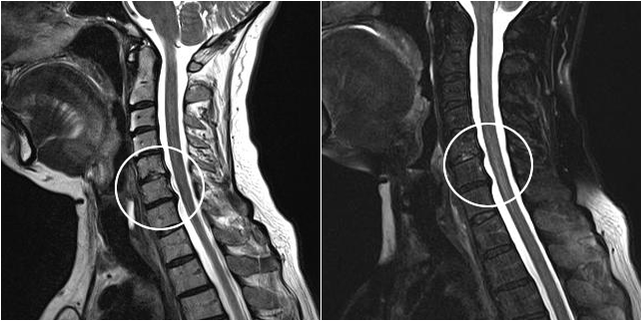

Diagnose einer Osteochondrose

Der Arzt muss eine möglichst vollständige Anamnese erheben. Bei der Untersuchung tastet der Facharzt die Bereiche ab, an denen der Schmerz am stärksten ausgeprägt ist.

Eine Röntgenuntersuchung wird Aufschluss geben. Besonders in den letzten Stadien der Krankheit.

Zu den modernen Diagnosemethoden gehören MRT und CT, mit denen Sie die Prozesse der Zerstörung von Knorpel- und Knochengewebe genauer untersuchen können. Darüber hinaus ist es mit dieser Technik bequem, Hernien und andere Weichteildefekte in der Nähe der Krankheitsquelle zu diagnostizieren.

Zur Differentialdiagnose der Osteochondrose der Brustregion wird ein EKG verwendet. Der Patient muss sich einer allgemeinen Blut- und Urinuntersuchung unterziehen.